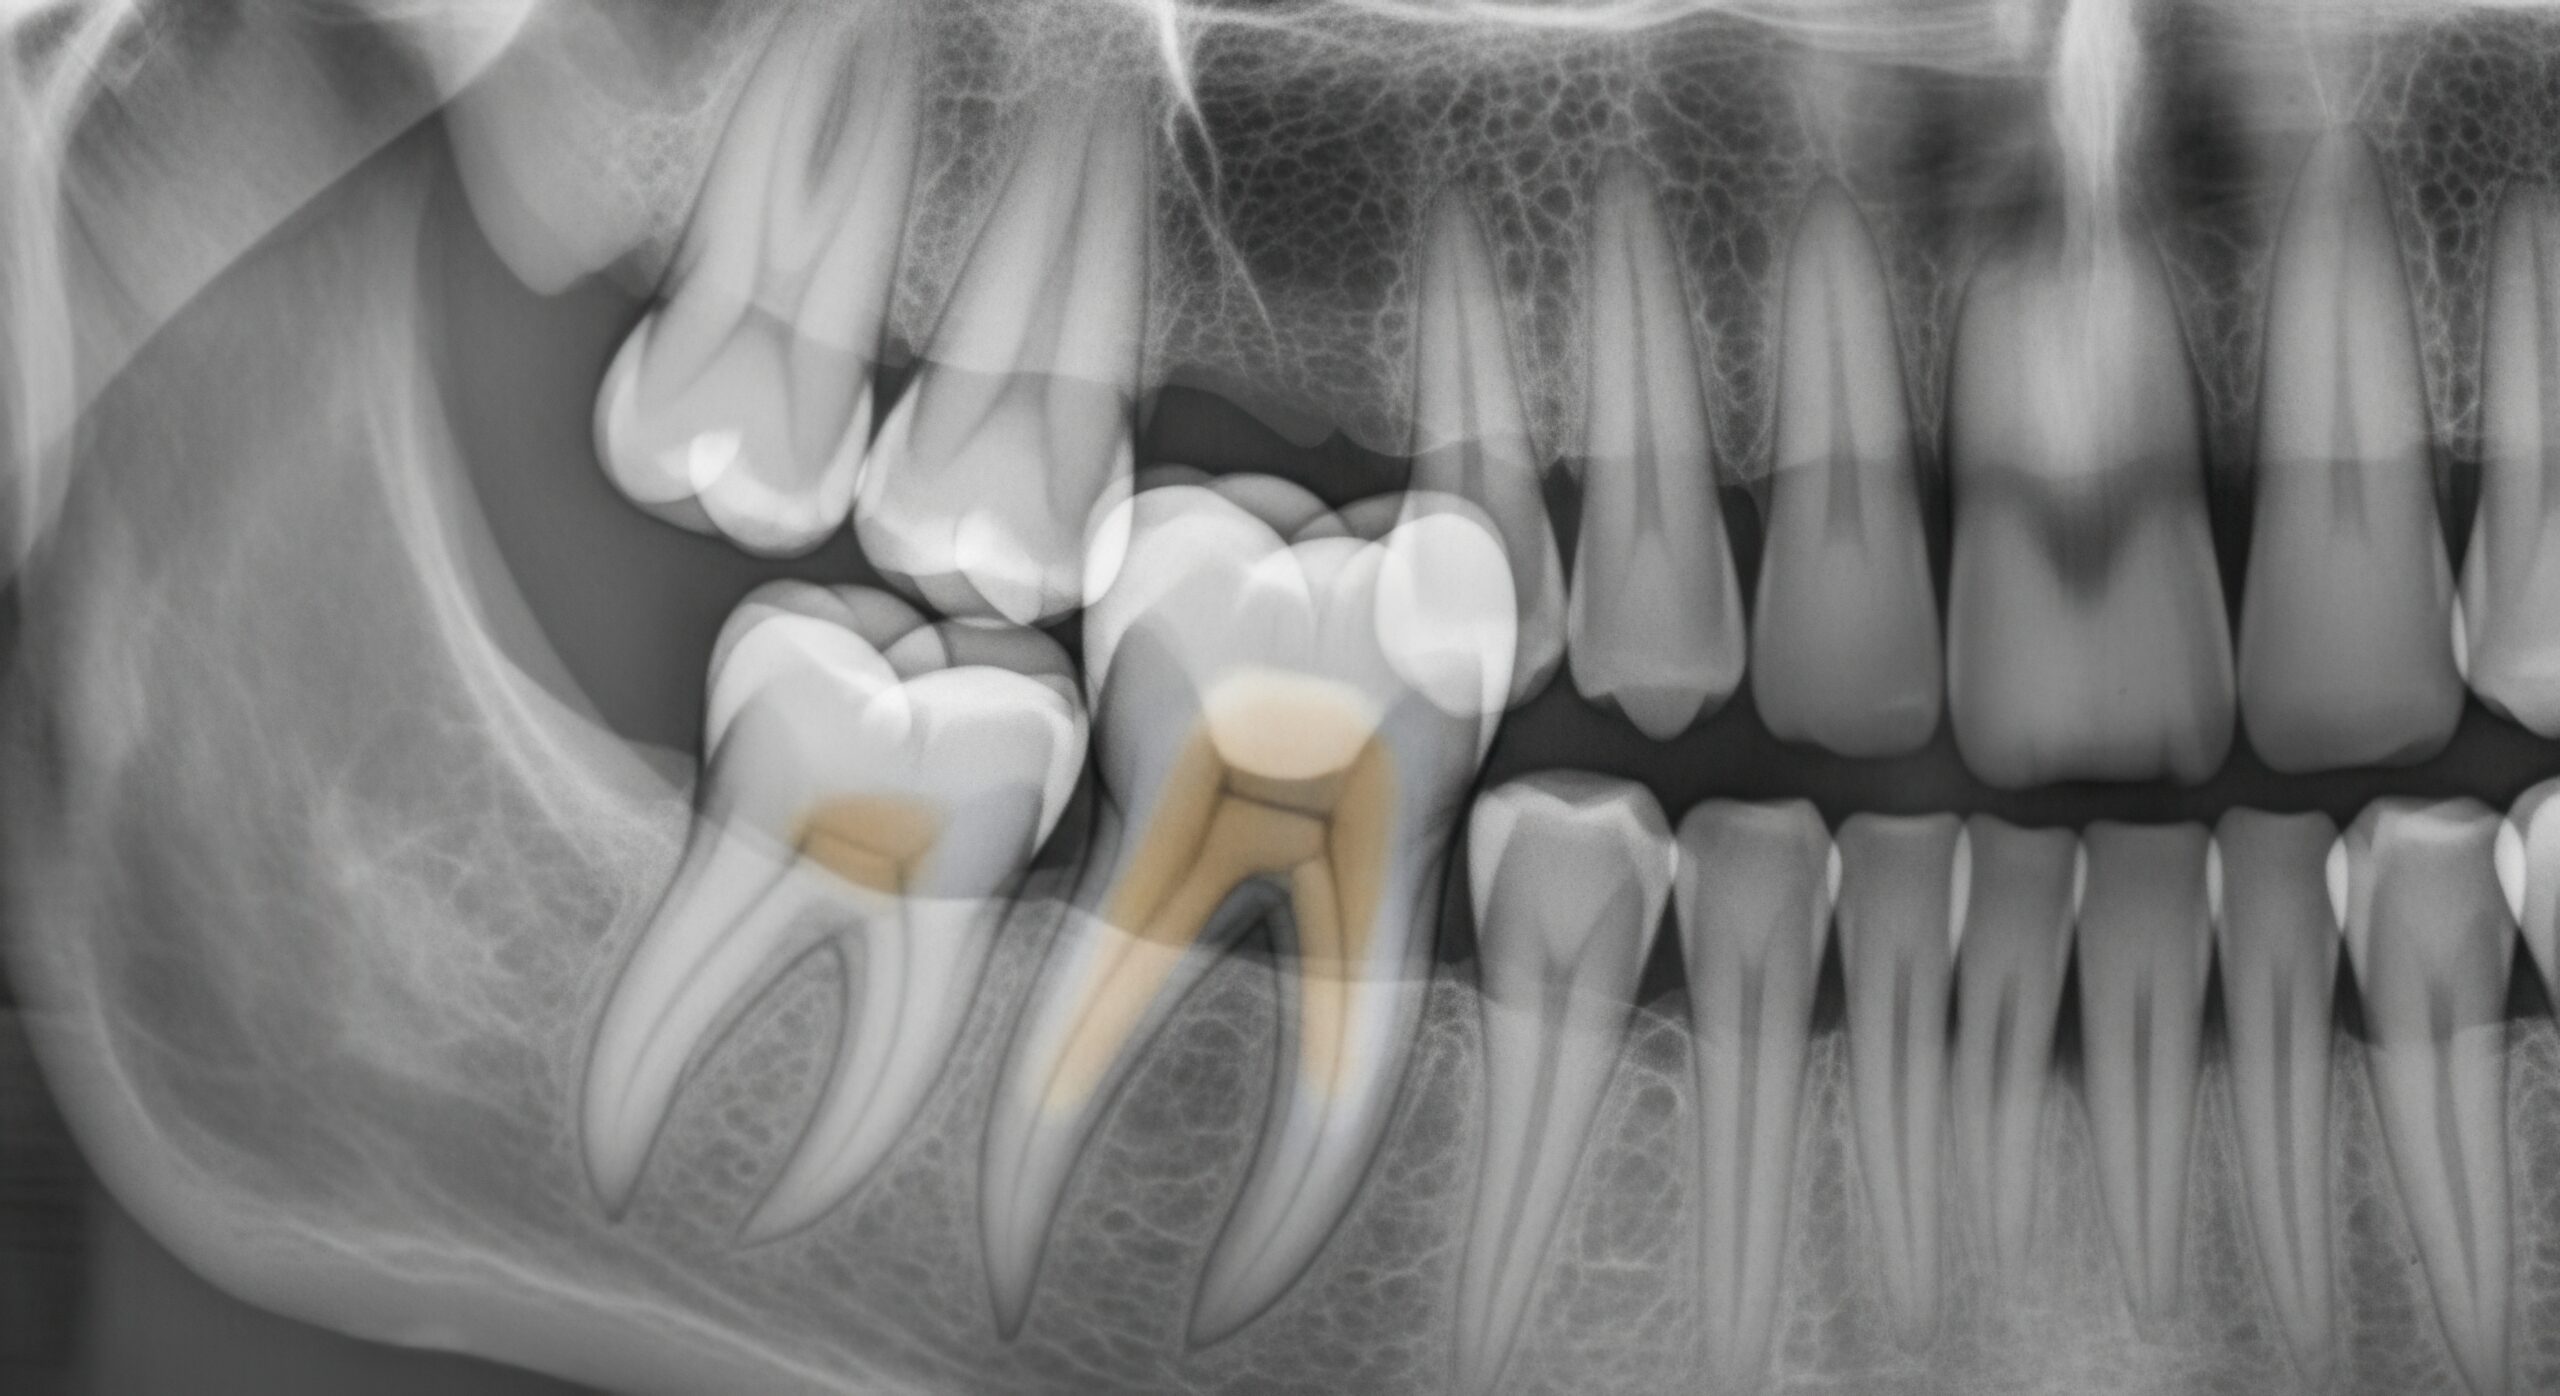

Advanced Imaging (3D CBCT When Indicated) Three-dimensional imaging allows precise evaluation of:

- Tooth orientation

- Root position

- Proximity to nerves and sinuses

- Surrounding bone anatomy

- This level of detail supports safer planning and risk assessment.